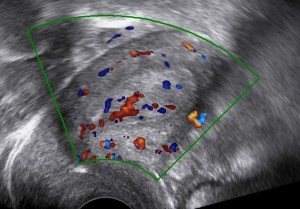

Ultrasound

The following ultrasound features may be associated with endometrial cancer:

- Thick endometrium (>3mm in the postmenopause)

- Large tumor volume

- Irregular endometrial-myometrial junction

- Non-uniform echogenicity

- Multiple vessels

Always bear in mind that endometrial cancer can also be found within adenomyosis.